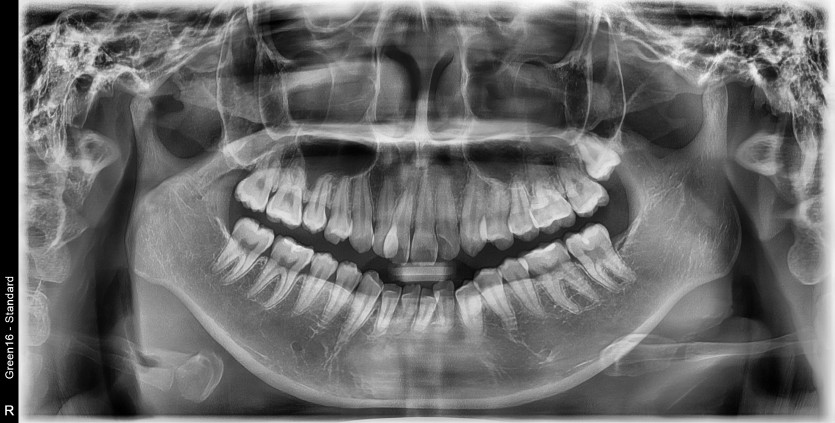

#28 사랑니 발치

구강 외과 전문의가 당일 발치했습니다.